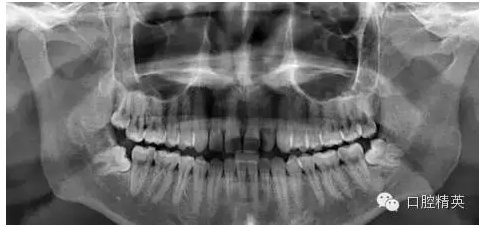

1、拔除前口內(nèi)全景片

診斷 : 下八近中中位阻生